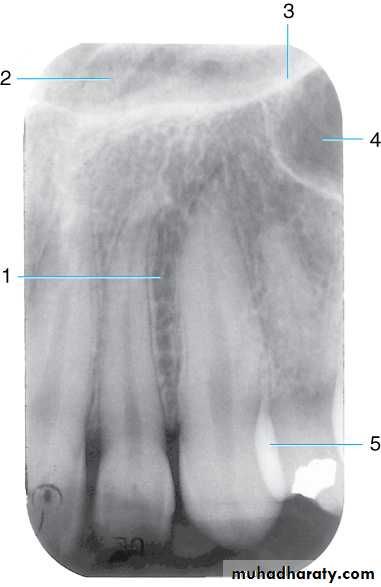

Drawing of maxillary canine area. The drawing shows the (1) lateral fossa, (2) nasal fossa, (3) inverted Y (intersection of the borders of nasal fossa and maxillary sinus), and (4) maxillary sinus. (5) Note the dense radiopaque area caused by overlapping of the mesial surface of the first premolar over the distal surface of the canine. This overlapping is common in this region of the oral cavity because of the curvature of the arch.

Radiograph of maxillary canine area. Shown are the (1) lateral fossa, (2) nasal fossa, (3) inverted Y, (4) maxillary sinus, and (5) dense radiopaque area caused by overlappingRadiographic Anatomy Basics